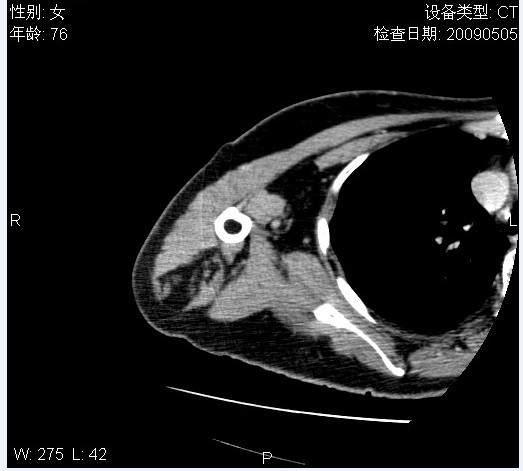

标题: CT19811:女,76岁,右上臂肿物1个月 [打印本页]

标题: CT19811:女,76岁,右上臂肿物1个月

使用了造影剂,可惜效果不太好

右肱骨上段软组织内见梭形低密度影,边界清楚,最长径约54mm.

病理结果:脂肪瘤。术中见肱骨骨膜受侵,有出血,量不详。

当时诊断意见:右肩三角肌内蔓状血管瘤(先天性动静脉瘘)。

本人对病理结果有个疑问:单纯的脂肪瘤内为什么有条状软组织影,那应该脂肪肉瘤才对啊?

该病例增强效果欠佳,由于经验欠缺,我们注射对比剂是由下肢足背静脉给药。注速2.0。虽然如此,但我们可以看到肿块内部条状软组织影是强化的,而且是连续的,并可见供血动脉是由腋动脉的其中一支即肩胛下动脉分出。从这些征象我们可以得出诊断:蔓状务血管瘤。

可病理偏偏为脂肪瘤,我怀疑取材有问题。因为蔓状血管瘤异常扩张的静脉外周是脂肪成分,它可以侵犯肌组织及骨骼。当取材于外周,那当然是脂肪瘤。此时我认为临床的最终诊断不应单从病理出发,应该综合考虑。